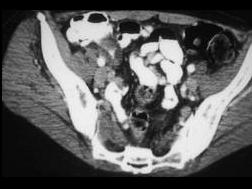

问题 男,42岁,右下腹痛、腹胀半年,无浅表淋巴结肿大,影像检查如图,最可能的诊断是 ( )

选项 A、肠结核 B、腹膜后纤维化 C、结肠癌 D、crohn病 E、淋巴瘤

答案 D